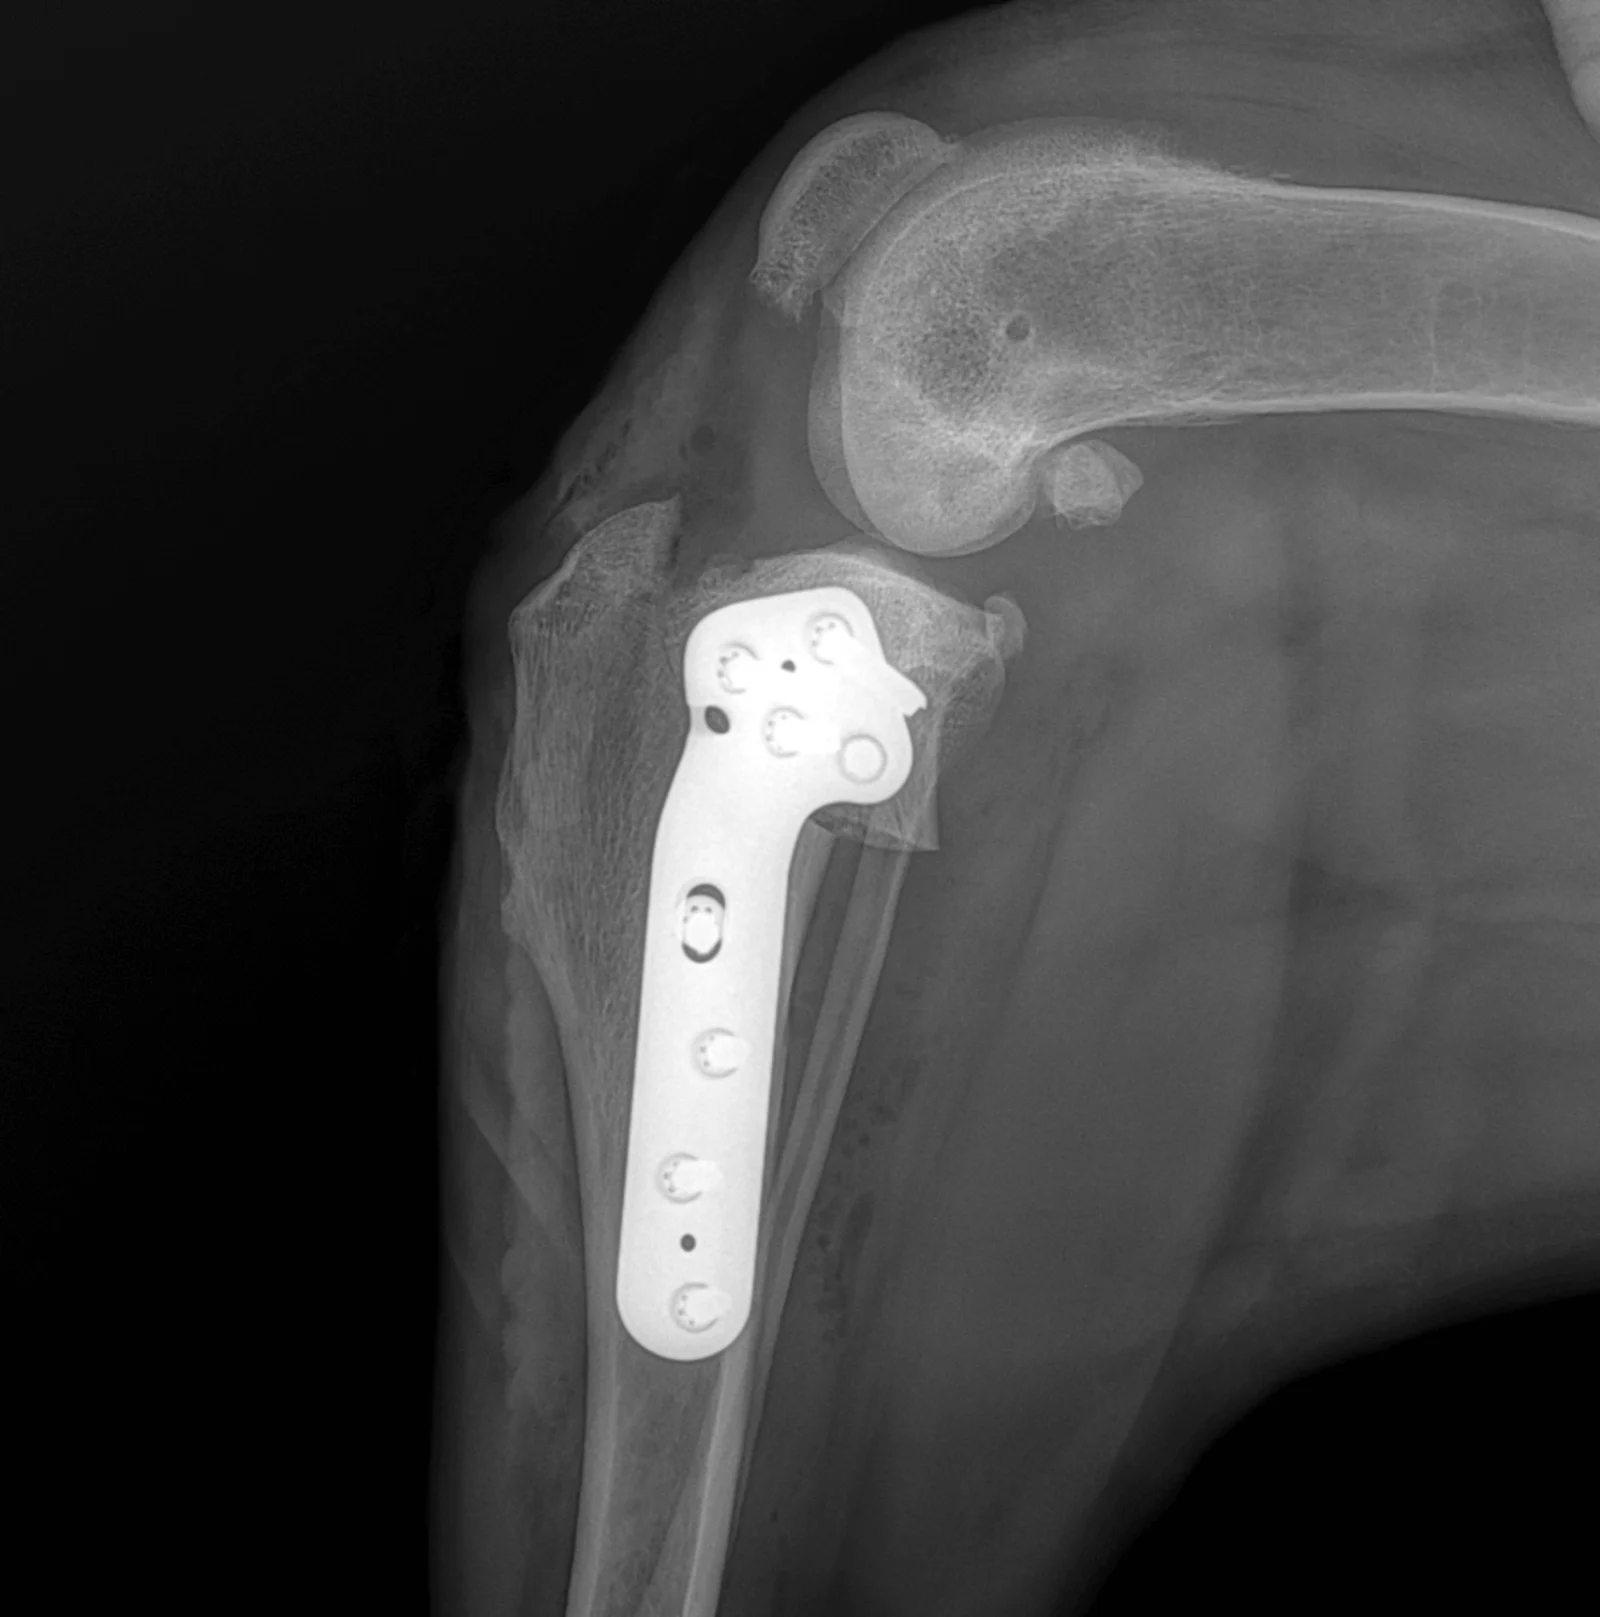

TPLO, Tibial Plateau Leveling Osteotomy

L’inclinaison du plateau tibial est modifiée chirurgicalement afin de changer l’axe de charge du genou. La fonction stabilisatrice du ligament croisé antérieur est ainsi neutralisée sans devoir le remplacer. Au vu du nombre croissant d’études objectives, la TPLO est la seule méthode ayant montré un niveau de charge comparable à celui du membre sain. Elle est considérée comme le standard d’or international de la chirurgie du ligament croisé chez le chien et convient aux chiens de toutes tailles.

Radiographie postopératoire de la technique TPLO. On voit le plateau tibial pivoté, qui est fixé à l'aide d'une plaque spéciale.